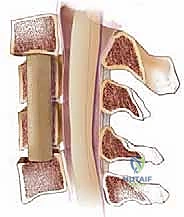

الخطوة 3: استئصال الأقراص الغضروفية وجسم الفقرة (Corpectomy)

باستخدام الميكروسكوب الجراحي وأدوات دقيقة جداً، يتم أولاً إزالة الأقراص الغضروفية أعلى وأسفل الفقرة المستهدفة. بعد ذلك، يتم استئصال جسم الفقرة العظمي المتضرر بعناية فائقة لفتح مساحة واسعة وتحرير الحبل الشوكي المضغوط.

الخطوة 4: زراعة الدعامة والدمج العظمي (Fusion)

بعد إزالة الفقرة، يتبقى فراغ كبير. لإعادة بناء العمود الفقري، يتم إدخال دعامة معدنية أو قفص من مادة (PEEK) أو التيتانيوم، مملوء بطعم عظمي (يؤخذ عادة من بنك العظام أو من حوض المريض، أو يتم استخدام بدائل عظمية صناعية). هذه الدعامة تحافظ على ارتفاع الرقبة الطبيعي.